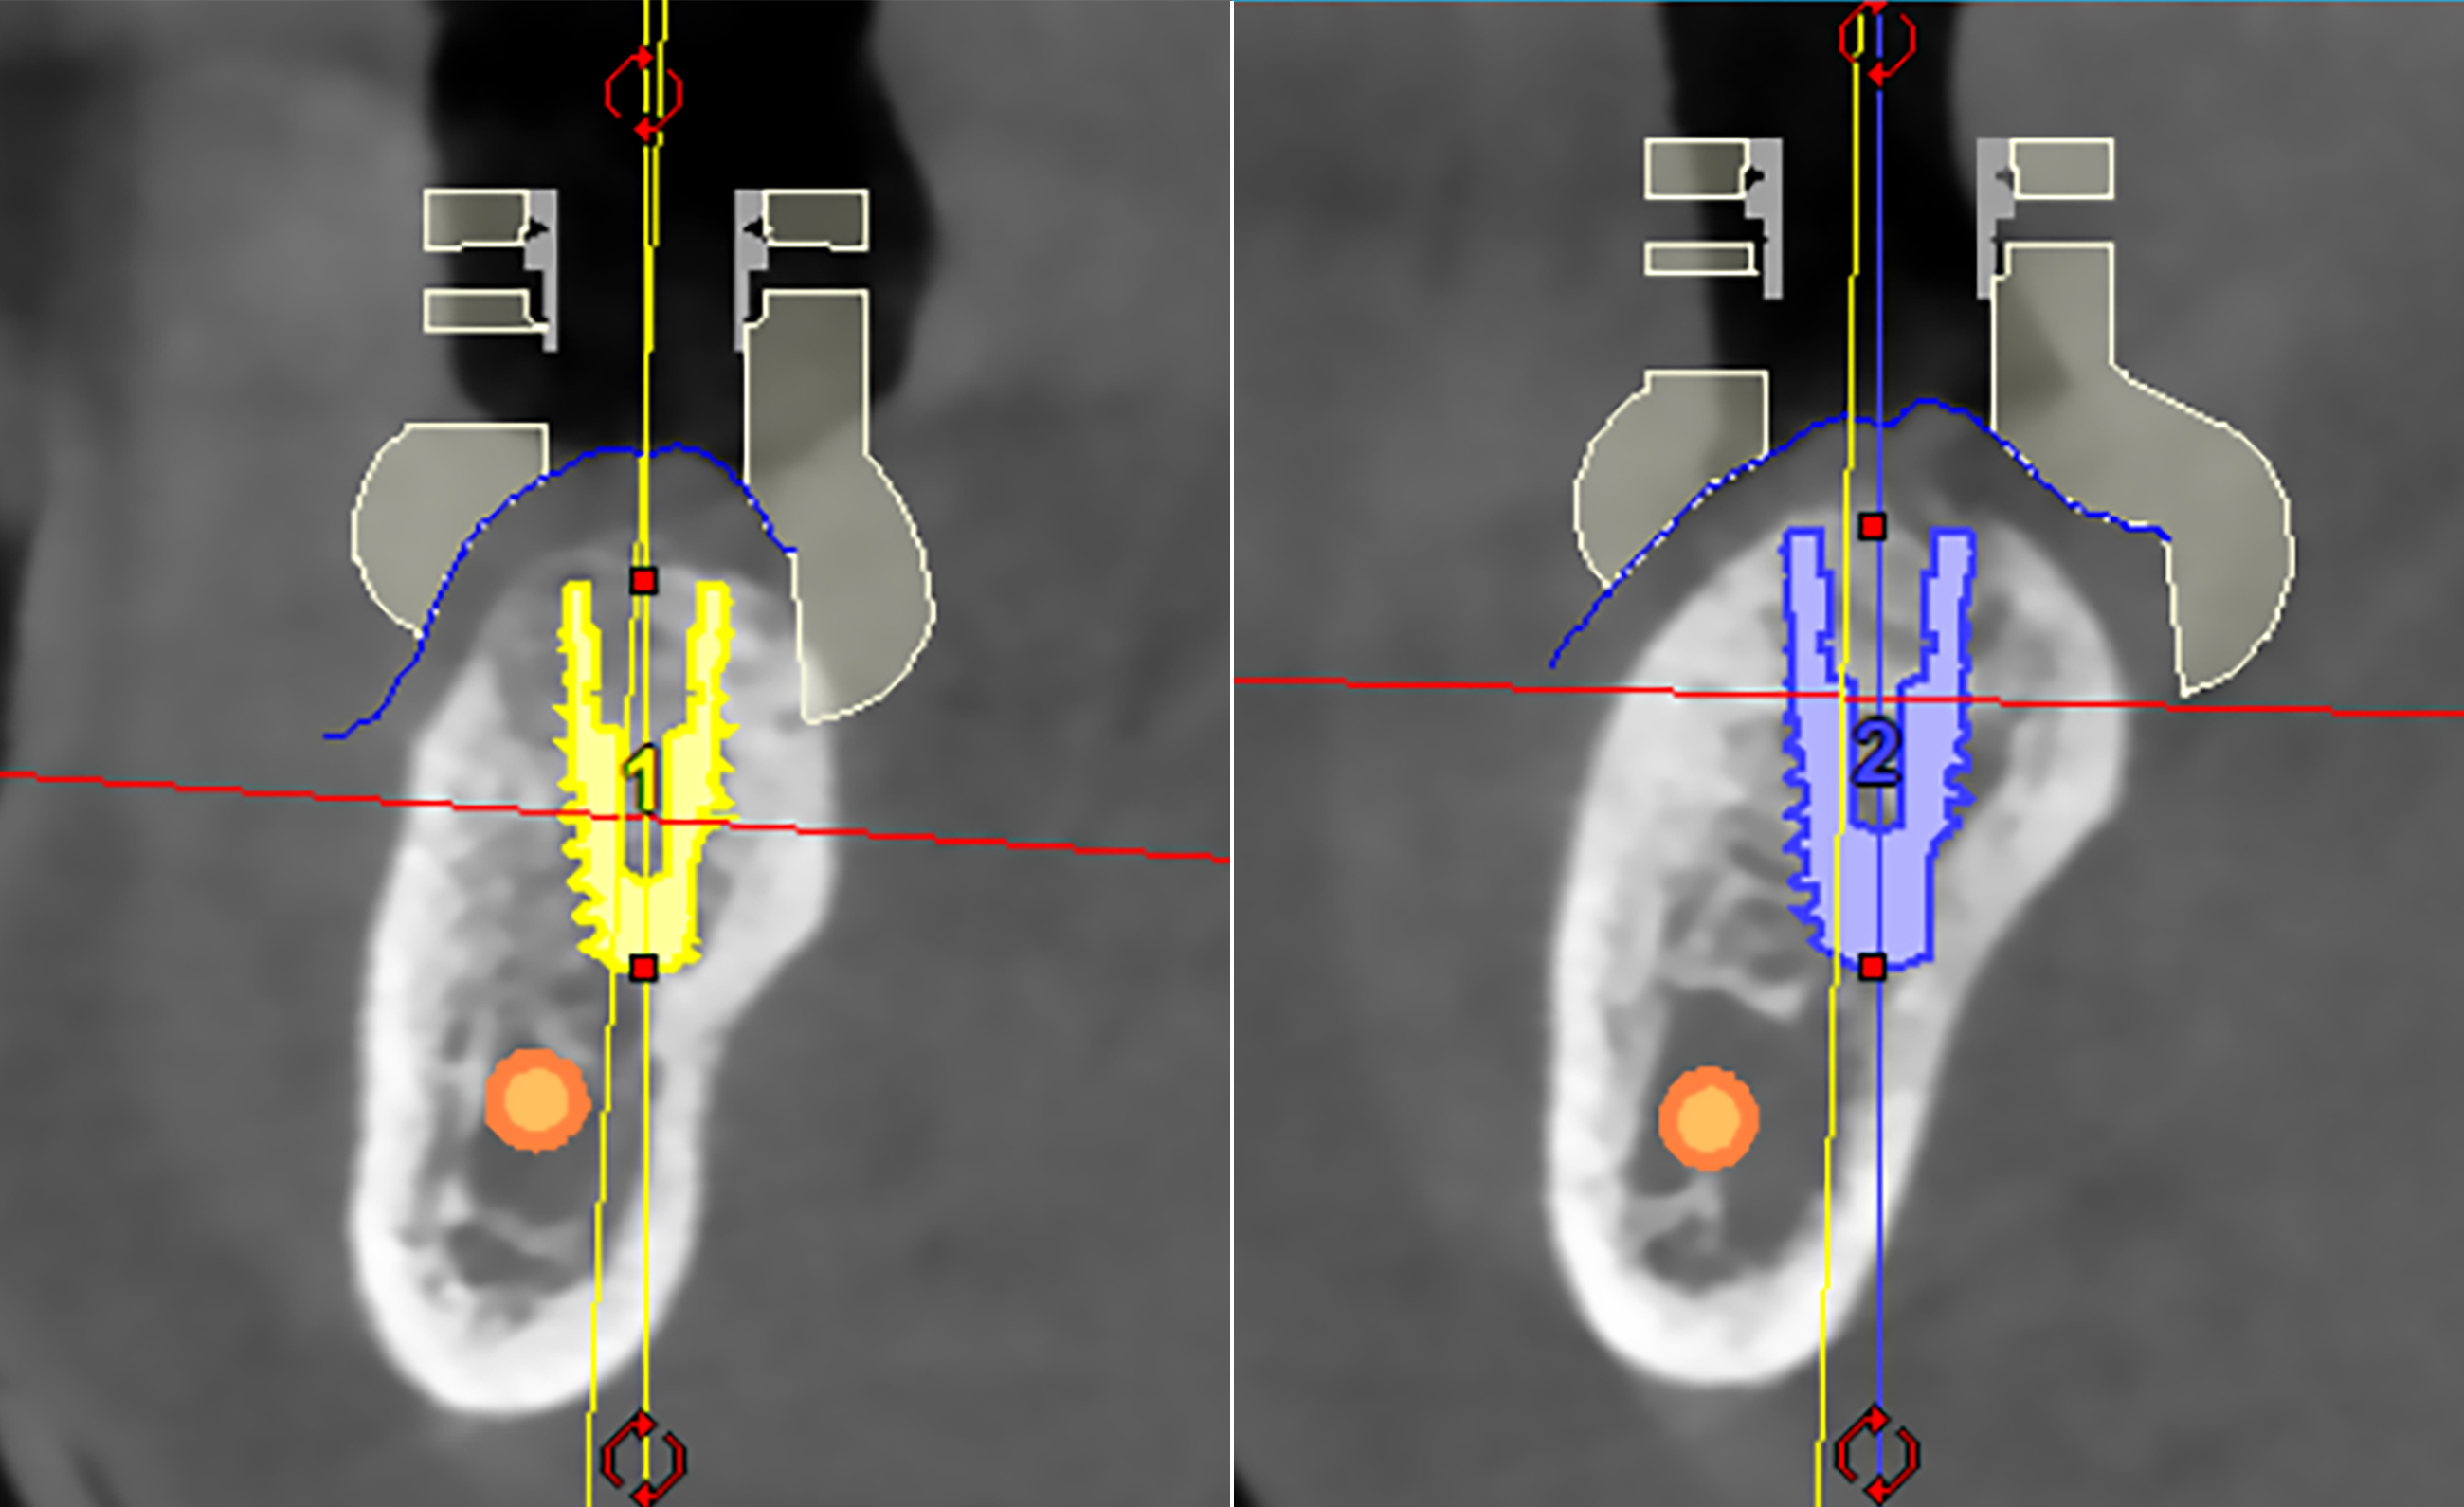

Με βάση την CBCT της κάτω γνάθου, προχωρήσαμε στον εικονικό σχεδιασμό των εμφυτευμάτων μέσω ειδικού προεγχειρητικού λογισμικού. Αξιολογήθηκε το ύψος, το πάχος και η ποιότητα του οστού, καθώς και η σχέση με κρίσιμες ανατομικές δομές όπως το κάτω φατνιακό νεύρο.

3D αξονική τομογραφία – Πανοραμική και εγκάρσια τομή της κάτω γνάθου της ασθενούς - Η τοποθέτηση των δύο εμφυτευμάτων έγινε στις ιδανικότερες θέσεις, με τη βοήθεια εξειδικευμένου λογισ�μικού χειρουργικού σχεδιασμού που χρησιμοποιούμε για την ακρίβεια και την ασφάλεια κάθε εμφυτευματικού περιστατικού

3D αξονική τομογραφία – Εγκάρσιες τομές της κάτω γνάθου της ασθενούς.

Απεικονίζονται τα δύο εμφυτεύματα που τοποθετήθηκαν με τη βοήθεια εξειδικευμένου προεγχειρητικού λογισμικού. Μέσω της ανάλυσης μπορούμε να αξιολογήσουμε τη θέση τους στο οστό, τον προσανατολισμό και τις μεταξύ τους κλίσεις, καθώς και την πιθανή γειτνίασή τους με σημαντικά ανατομικά μόρια